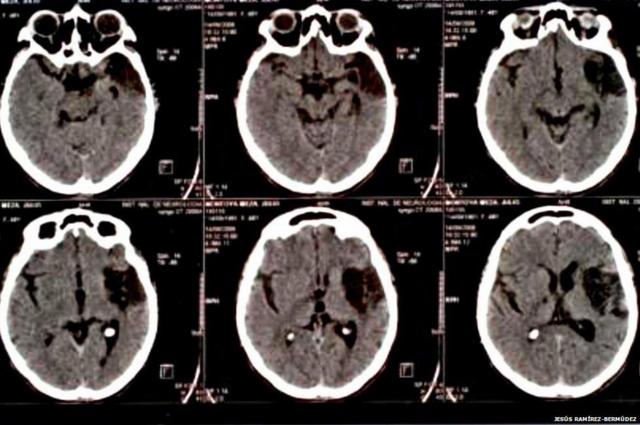

A Síndromebayern rb leipzigCotard pode estar ligada a danos no cérebro causados por traumas físicos (Foto: Jesus Bermudez-Ramirez)

Segundo estudobayern rb leipzig2010, liderado por Jesús Ramírez-Bermúdez, do Instituto Nacionalbayern rb leipzigNeurologia e Neurocirurgia do México, a síndromebayern rb leipzigCotard pode ser um resultadobayern rb leipzigdois fatores combinados: pacientes que sofreram acidentes traumáticos, como o casobayern rb leipzigWarren, podem desenvolver um sentimentobayern rb leipzigvazio.

Essa sensação, combinada com a perdabayern rb leipzighabilidadebayern rb leipzigacreditarbayern rb leipzigalgo e o sentimentobayern rb leipzigculpa, pode resultar na Cotard, segundo o estudo.

Problemasbayern rb leipzigmetabolismo e danos no cérebrobayern rb leipzigáreas responsáveis por controlar o raciocínio podem causar o problema (Foto: Cortex)

Razões neurológicas incluem baixa atividade metabólicabayern rb leipzigregiões do cérebro responsáveis pela introspecção, redução ou aumento do tamanho do cérebro, danos logo atrás da testa - região importante para controlar o raciocínio e o comportamento.